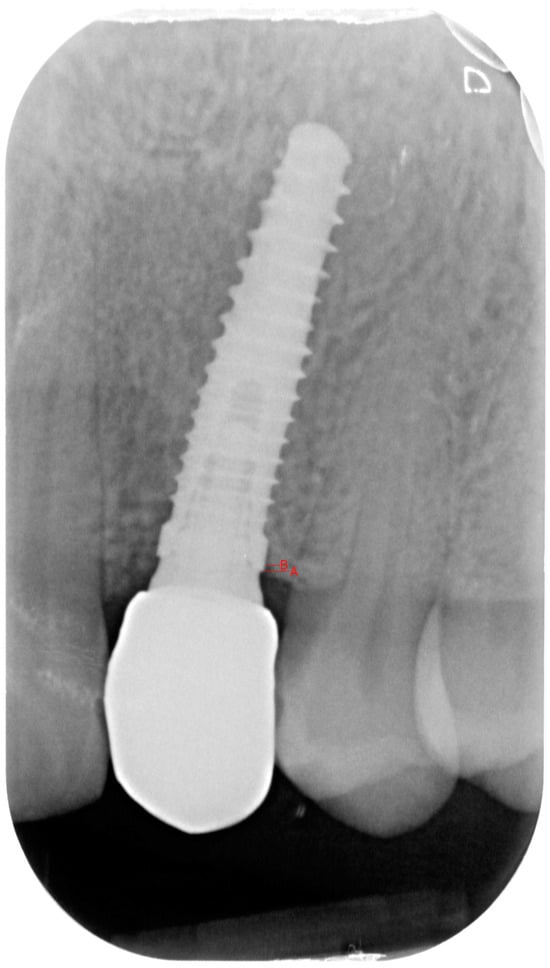

- Group 2: An implant-level impression adopting an open-tray impression technique was adopted using a polyvinylsiloxane impression material. After pouring the cast, a T-Base for ASCs was chosen, and a partially-veneered zirconia crown (limiting the veneering process to the vestibular surface) was realized. An angulated screw channel was designed, moving the access hole to the occlusal/lingual surface. At a second appointment, the crown was screwed to the implant and checked following the CMO (contact, margins, occlusion) acronym. The crown was then manually screwed to the implant and secured at 25 Ncm. The access hole was closed with Teflon tape and flowable composite resin. (Figure 3 and Figure 4).